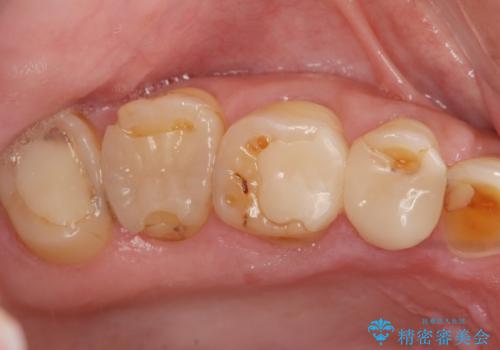

- 重度の歯ぎしり癖で歯がすり減り、見た目・噛み合わせの改善とこれ以上すり減る前の処置を希望され来院されました。

高さが短くなってしまった歯は、安定したクラウンを作るのが難しいため歯ぐきを下げる歯周外科を行ったのちに強度に優れるフルジルコニアクラウンで補綴治療を行います。

すり減ってしまった歯に対し、歯冠長延長術(歯周外科)を行うことで安定したクラウンを製作・装着することが出来ました。